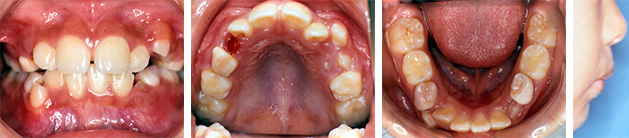

叢生が強い症例

Step1: 拡大

Step2: 前歯の並べ替え

| 年齢性別 | 9歳1か月 女の子 |

|---|---|

| はじめのご相談 | 歯が重なって生えてきているとのことでご相談いただきました。 |

| カウンセリング・診断結果 | 骨格的な問題はないが、上下V-shaped archで永久歯の生えるスペースがなく八重歯となっている状態でした。機能的な問題として口唇閉鎖不全と低位舌が見られました。口元は特に問題はありませんでした。 治療は、歯列の拡大をおこない永久歯の萌出スペースを作り、可及的に非抜歯治療を提案しました。 |

| 行ったご提案・診断内容 | 成長期にアーチ形態の修正・拡大(QH・BH)で永久歯の萌出スペースをつくり、上下前歯の調整(ブラケット)を行いました。舌などの機能改善はMFTで行いました。 咬合治療はモノブロック装置を先行させ、必要によりマルチブラケット法へ移行予定です。 |

| 治療期間 | 2年9か月 |

| おおよその費用 | 90万円+TAX |

| 術後の経過や現在の様子 | 横顔も問題なく咬合とともに経過良好です。保定装置およびMFTで経過観察しています。 |

| 治療のリスク | 凸凹(でこぼこ)や口元の突出が残る場合は、抜歯治療へ移行します。 その他、矯正治療に伴うリスクとして、歯ブラシ不足による虫歯・歯周病、装置による違和感・痛み、口内炎、話しにくい・食べにくい、歯肉退縮、歯髄壊死、歯根吸収、顎関節症の悪化などがあります。 |